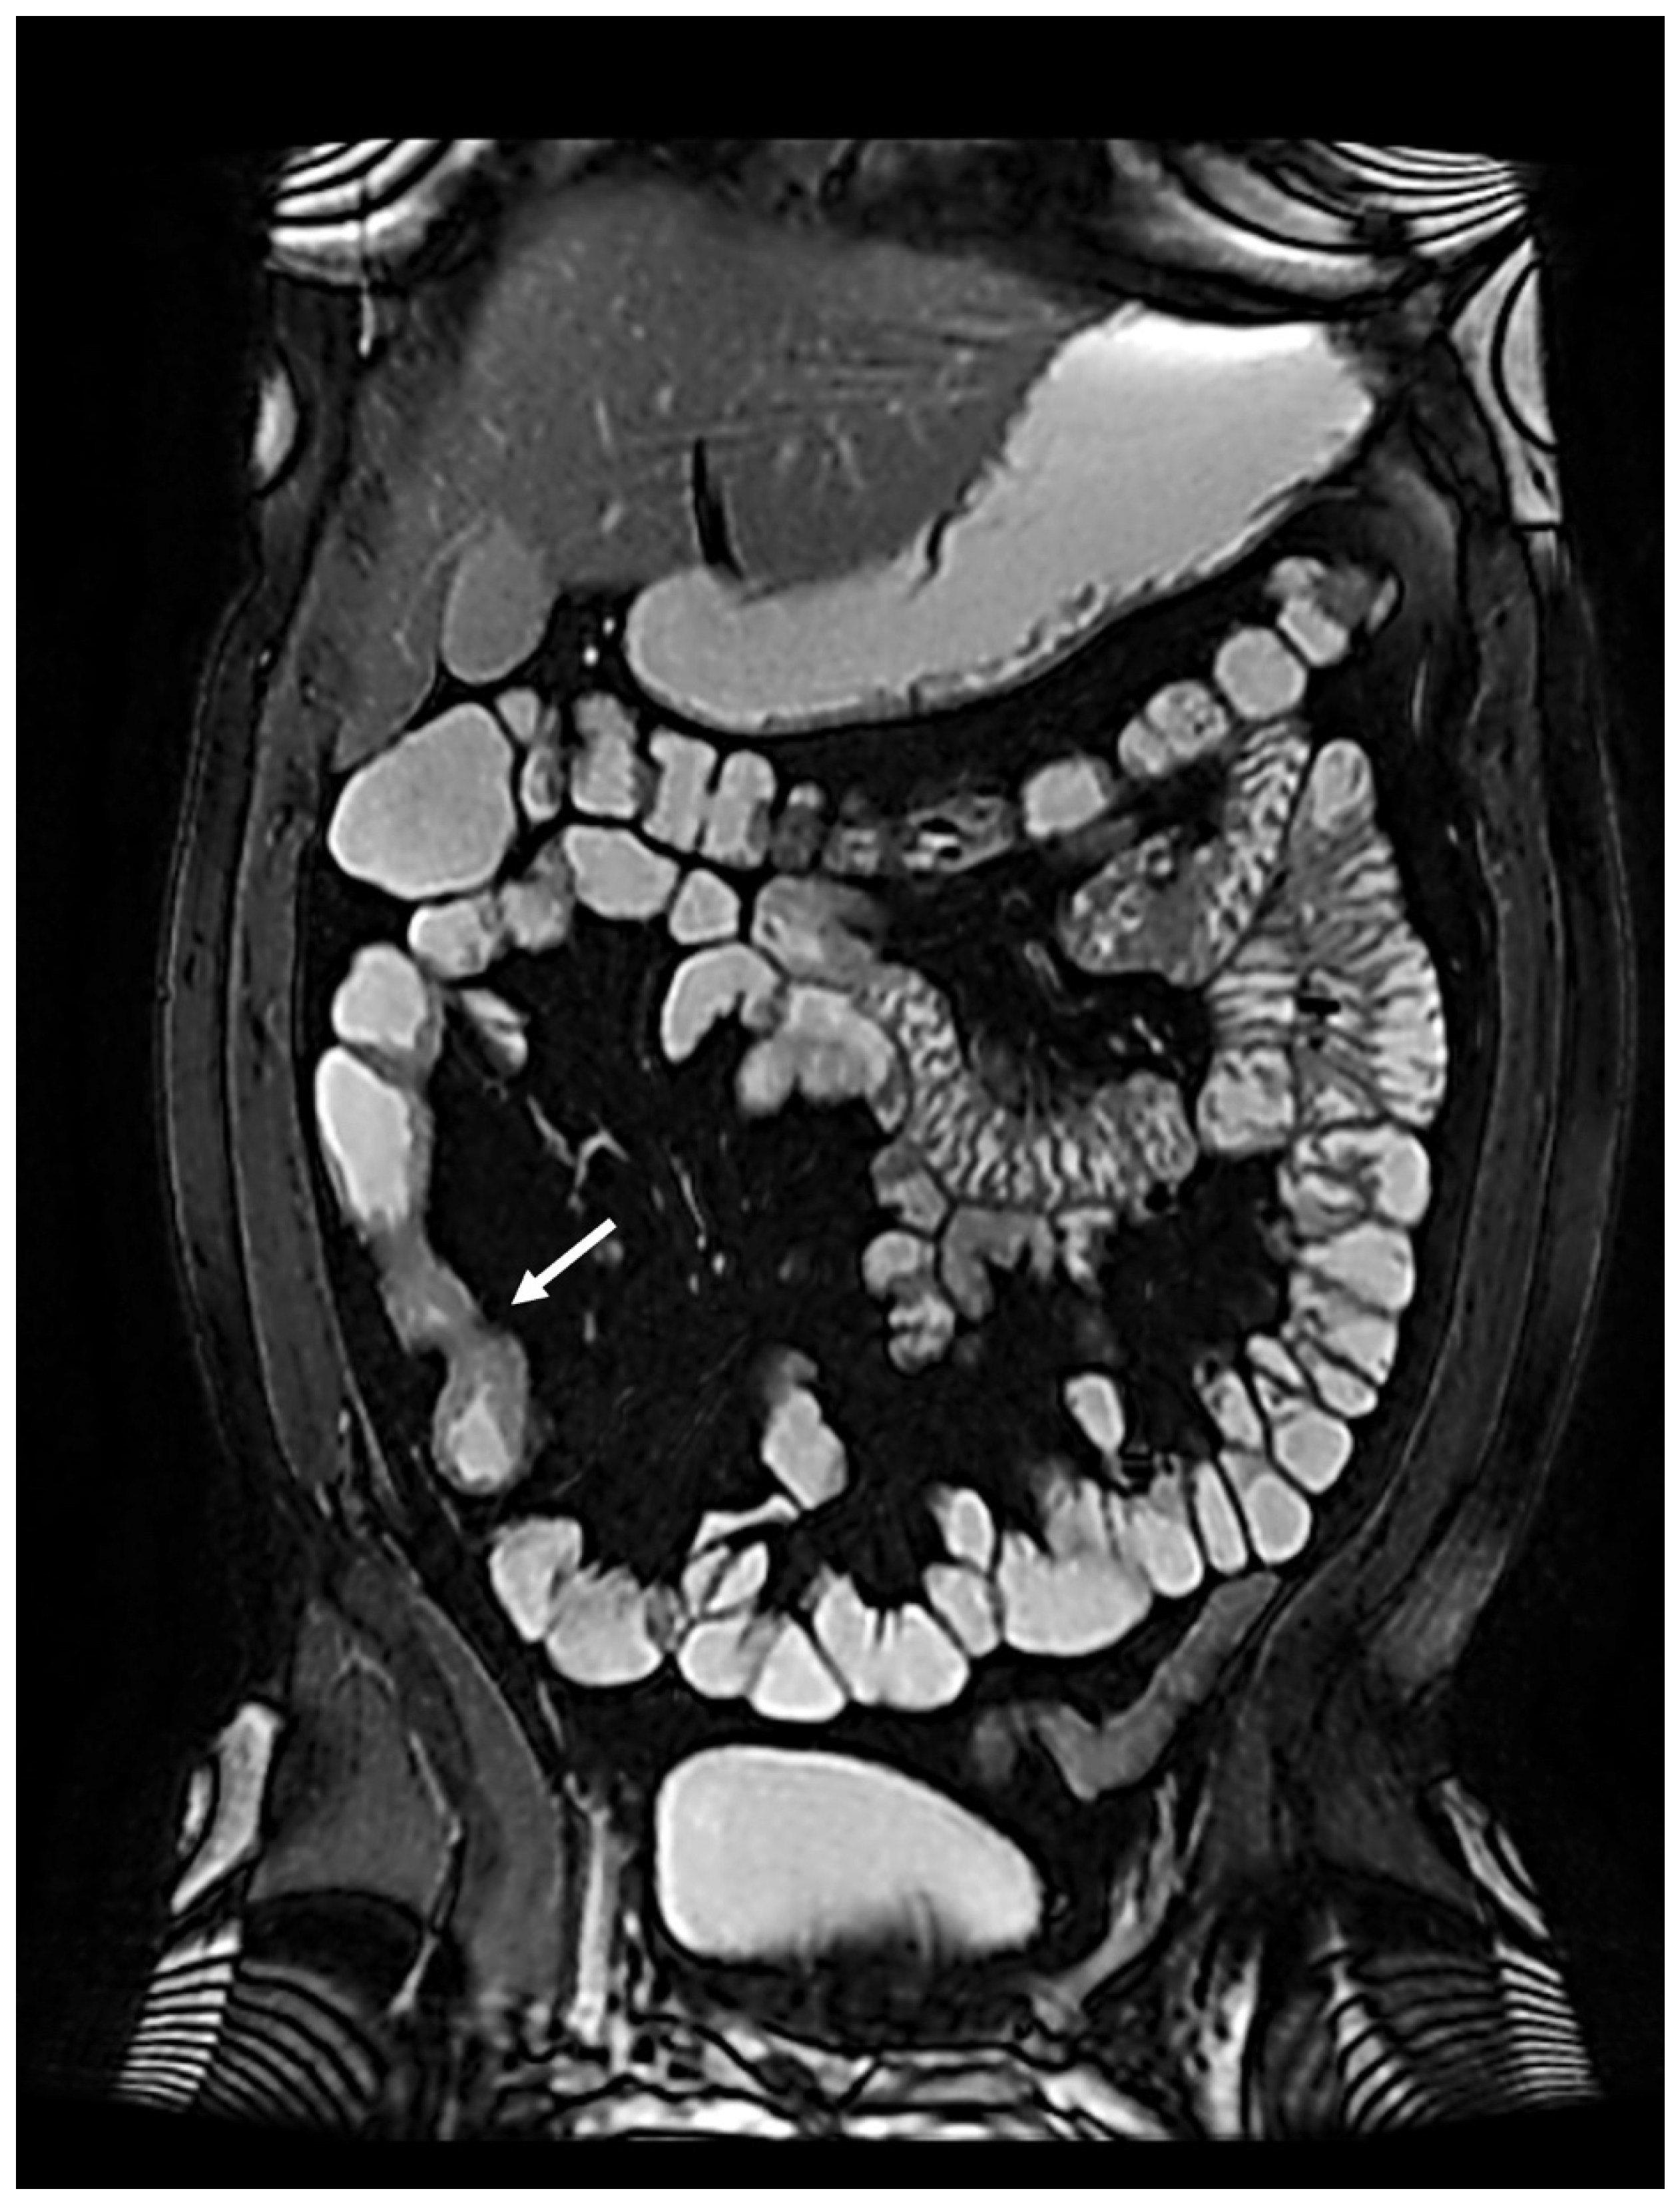

In April 2022, endoscopic evaluation was performed (Figure 1), without showing any abnormalities in mucosal anastomosis but mild mucosal erythema of the left colon.

Figure 1. Normal anastomotic picture at endoscopy.